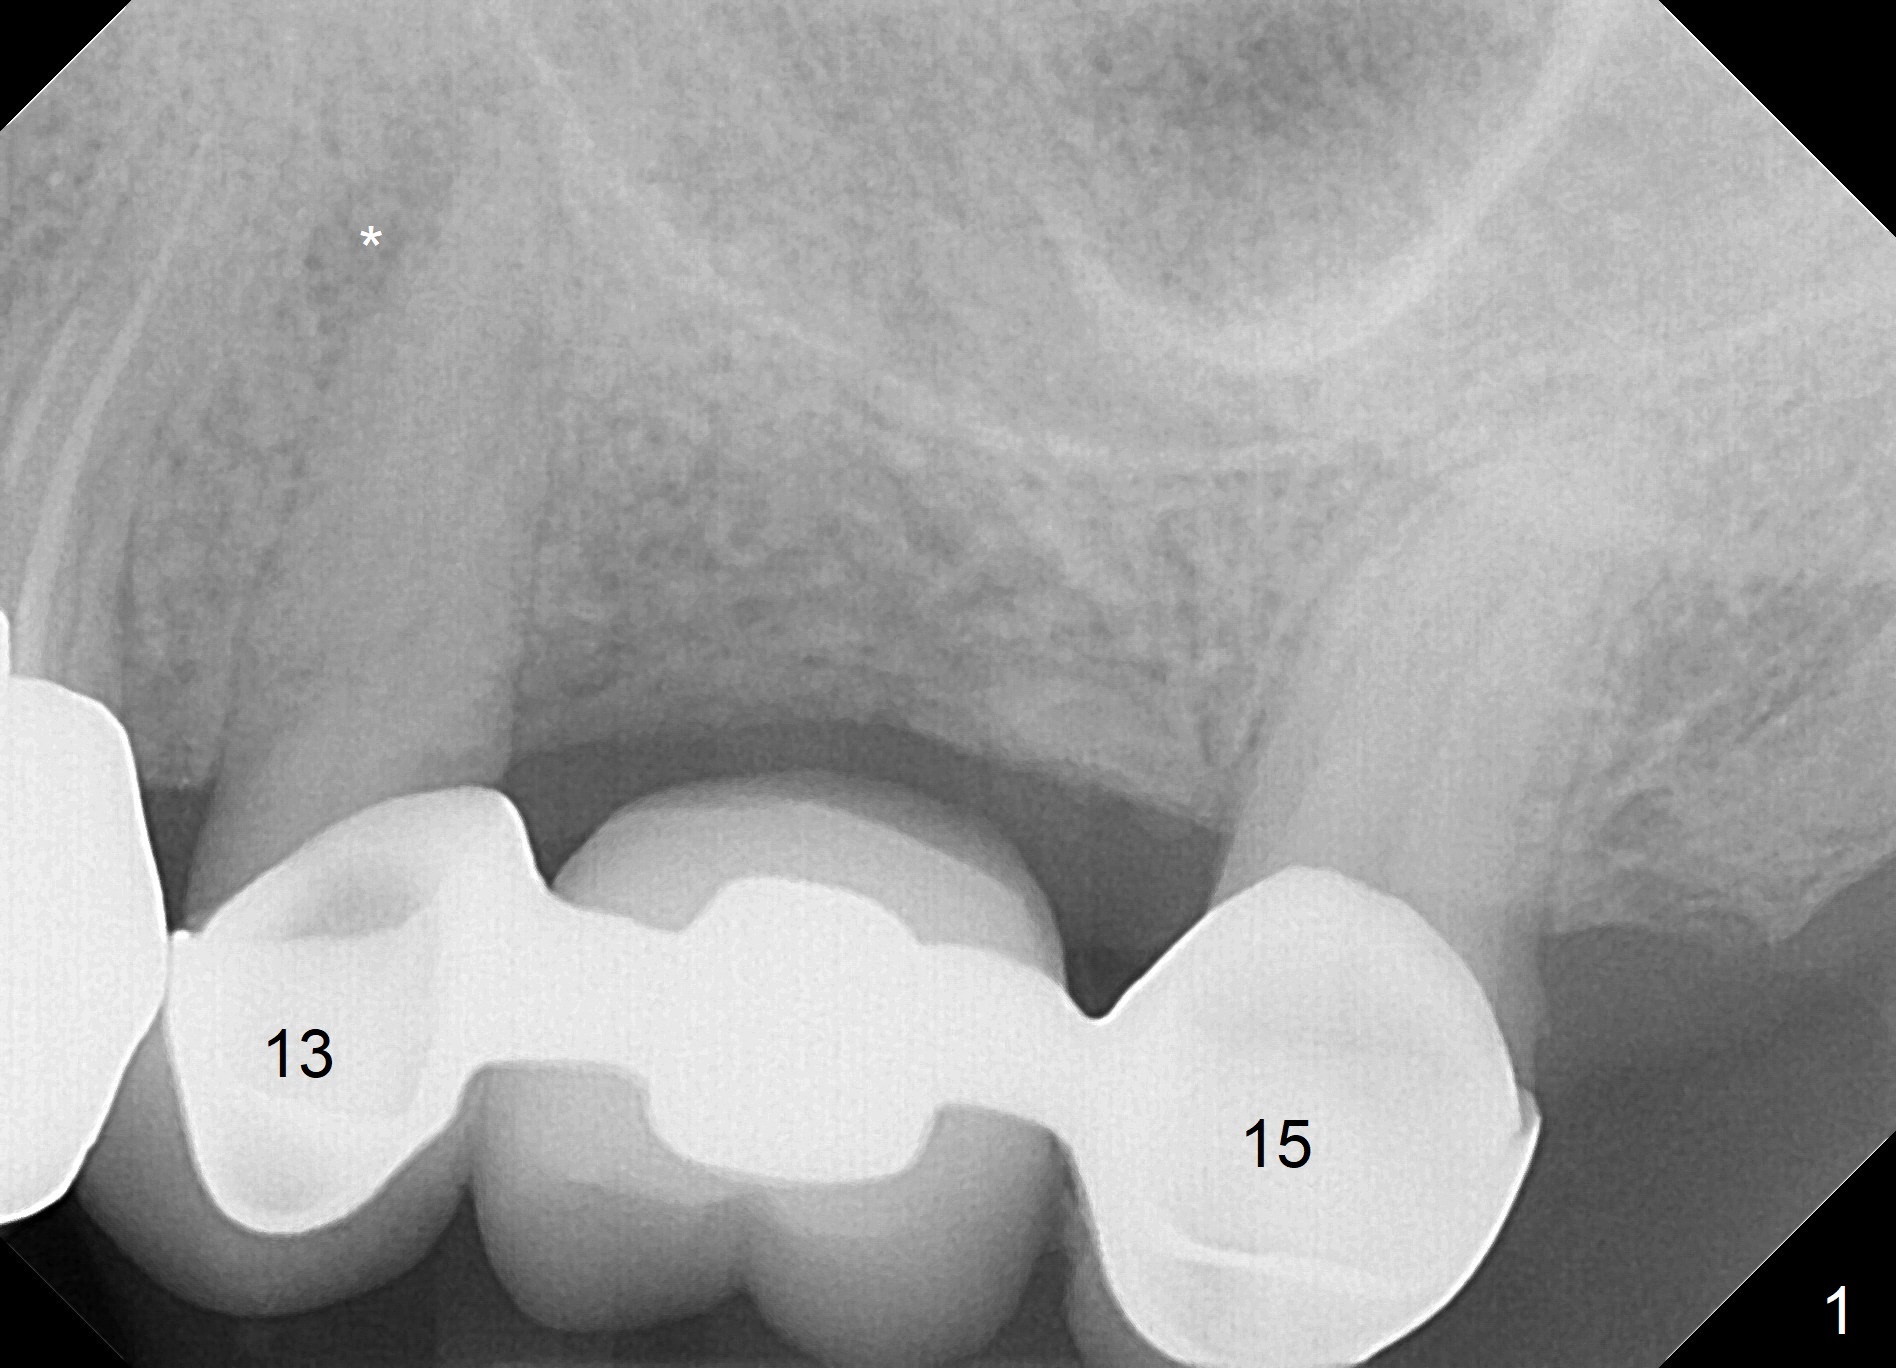

A 75-year-old man came to our office with symptom related to #13-15 FPD 2 months ago (Fig.1). Note periapical radiolucency (PARL, *) associated with the tooth #13. He has a RPD to replace #2 and 3. Last Friday, the crown and post at #12 dislodged (Fig.2). To reduce infection from the neighboring tooth (*), osteotomy will be established in the mesial slope of the socket (red line). The RPD has clasps at #4; the immediate provisional should be wide enough to cover the socket, while it must be skinny enough coronally to avoid contact when the patient puts on and takes off the RPD. The 1st premolar is still in cosmetic zone. If the implant is placed buccal, use a gold-coated abutment. Return to Upper Premolar Immediate Implant, IBS, Clindamycin Xin Wei, DDS, PhD, MS 1st edition 08/25/2017, last revision 11/10/2018